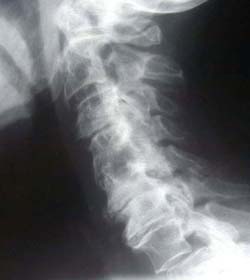

Phase Three Subluxation Degeneration

Phase Three degeneration develops when subluxations persist for 40 to 65 years. All findings from the previous stages now become more severe:

• Significant loss of normal spinal curvature

• Severely altered or collapsed disc spaces

• Extensive calcium deposits or bony overgrowths ("spurs" or "lipping")

• Marked reduction in movement

• Changes in the shape and integrity of the vertebrae

Most individuals in Phase Three experience symptoms, stiffness, or functional limitations.

Chiropractic reconstructive care in Phase Three often ranges from 2.5 to 3.5 years.

Although calcium deposits may remain, improvements in function and mobility are still common — the goal becomes restoring as much quality of movement and life as possible.

Phase Four Subluxation Degeneration

Phase Four occurs when subluxations have been present for over 65 years. This is a severe stage of spinal degeneration and often affects both longevity and quality of life. X-rays typically show:

• Extreme structural deformation

• Massive calcium buildup

• Virtually absent or blurred disc spaces

• Areas of the spine that appear fused

Patients in this stage usually have very limited mobility and may experience multiple related health challenges.

Although complete reconstruction may not be possible, chiropractic care can still aim to reduce subluxation where possible, improve comfort, and enhance remaining quality of life. Many patients in Phase Four still report meaningful improvements in pain, mobility and overall wellbeing.